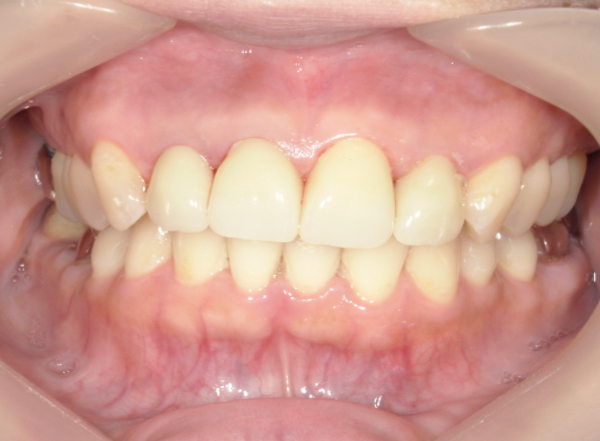

CASE1

セラミックを用いた虫歯治療

| 主訴 | 虫歯の治療と全体的な見た目の改善 |

|---|---|

| 治療期間 | 2ヶ月 |

| 治療費 | セラミック1本 88,000円〜165,000円(税込) デンタルローンで月3,000円から始められます |

| 治療の リスク | 治療には神経の治療や抜歯が必要な場合があります。 虫歯や歯周病を防ぐ為に、定期検診にご来院いただきます。 |